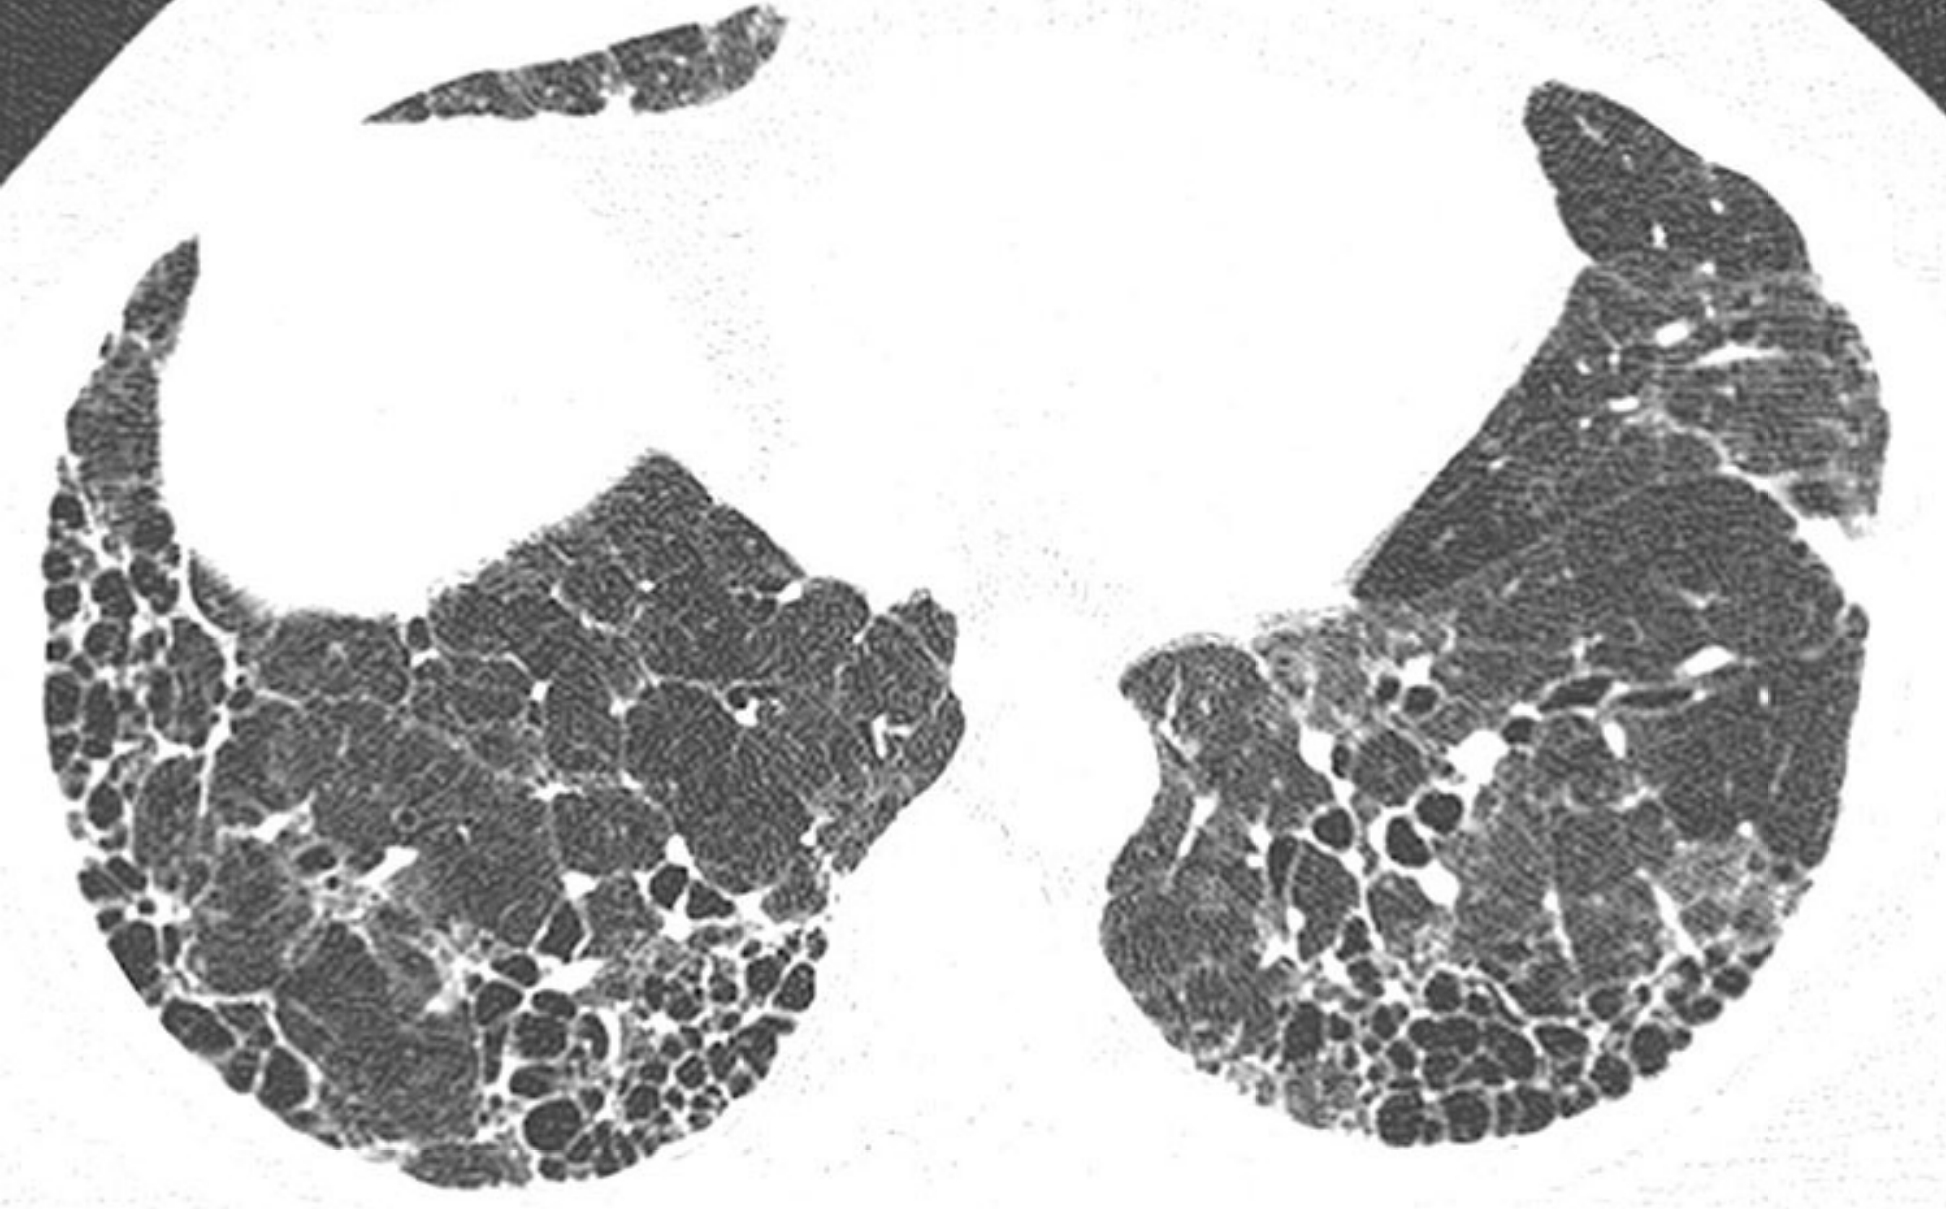

1d6b3eec372d7c316be21a0d6fbe74cc.jpg

家族性肺纤维化。

同一家族的2例家族性肺纤维化(A和B);活检证实,其组织学类型为普通型间质性肺炎(UIP)。

A. 1例患者表现为肺基底部分布为主的斑片状GGO和轻度牵拉性支气管扩张,B.另一患者表现为肺上叶和中央区分布为主的网状影、牵拉性支气管扩张和肺囊肿。家族性肺纤维化患者的HRCT表现通常不典型。